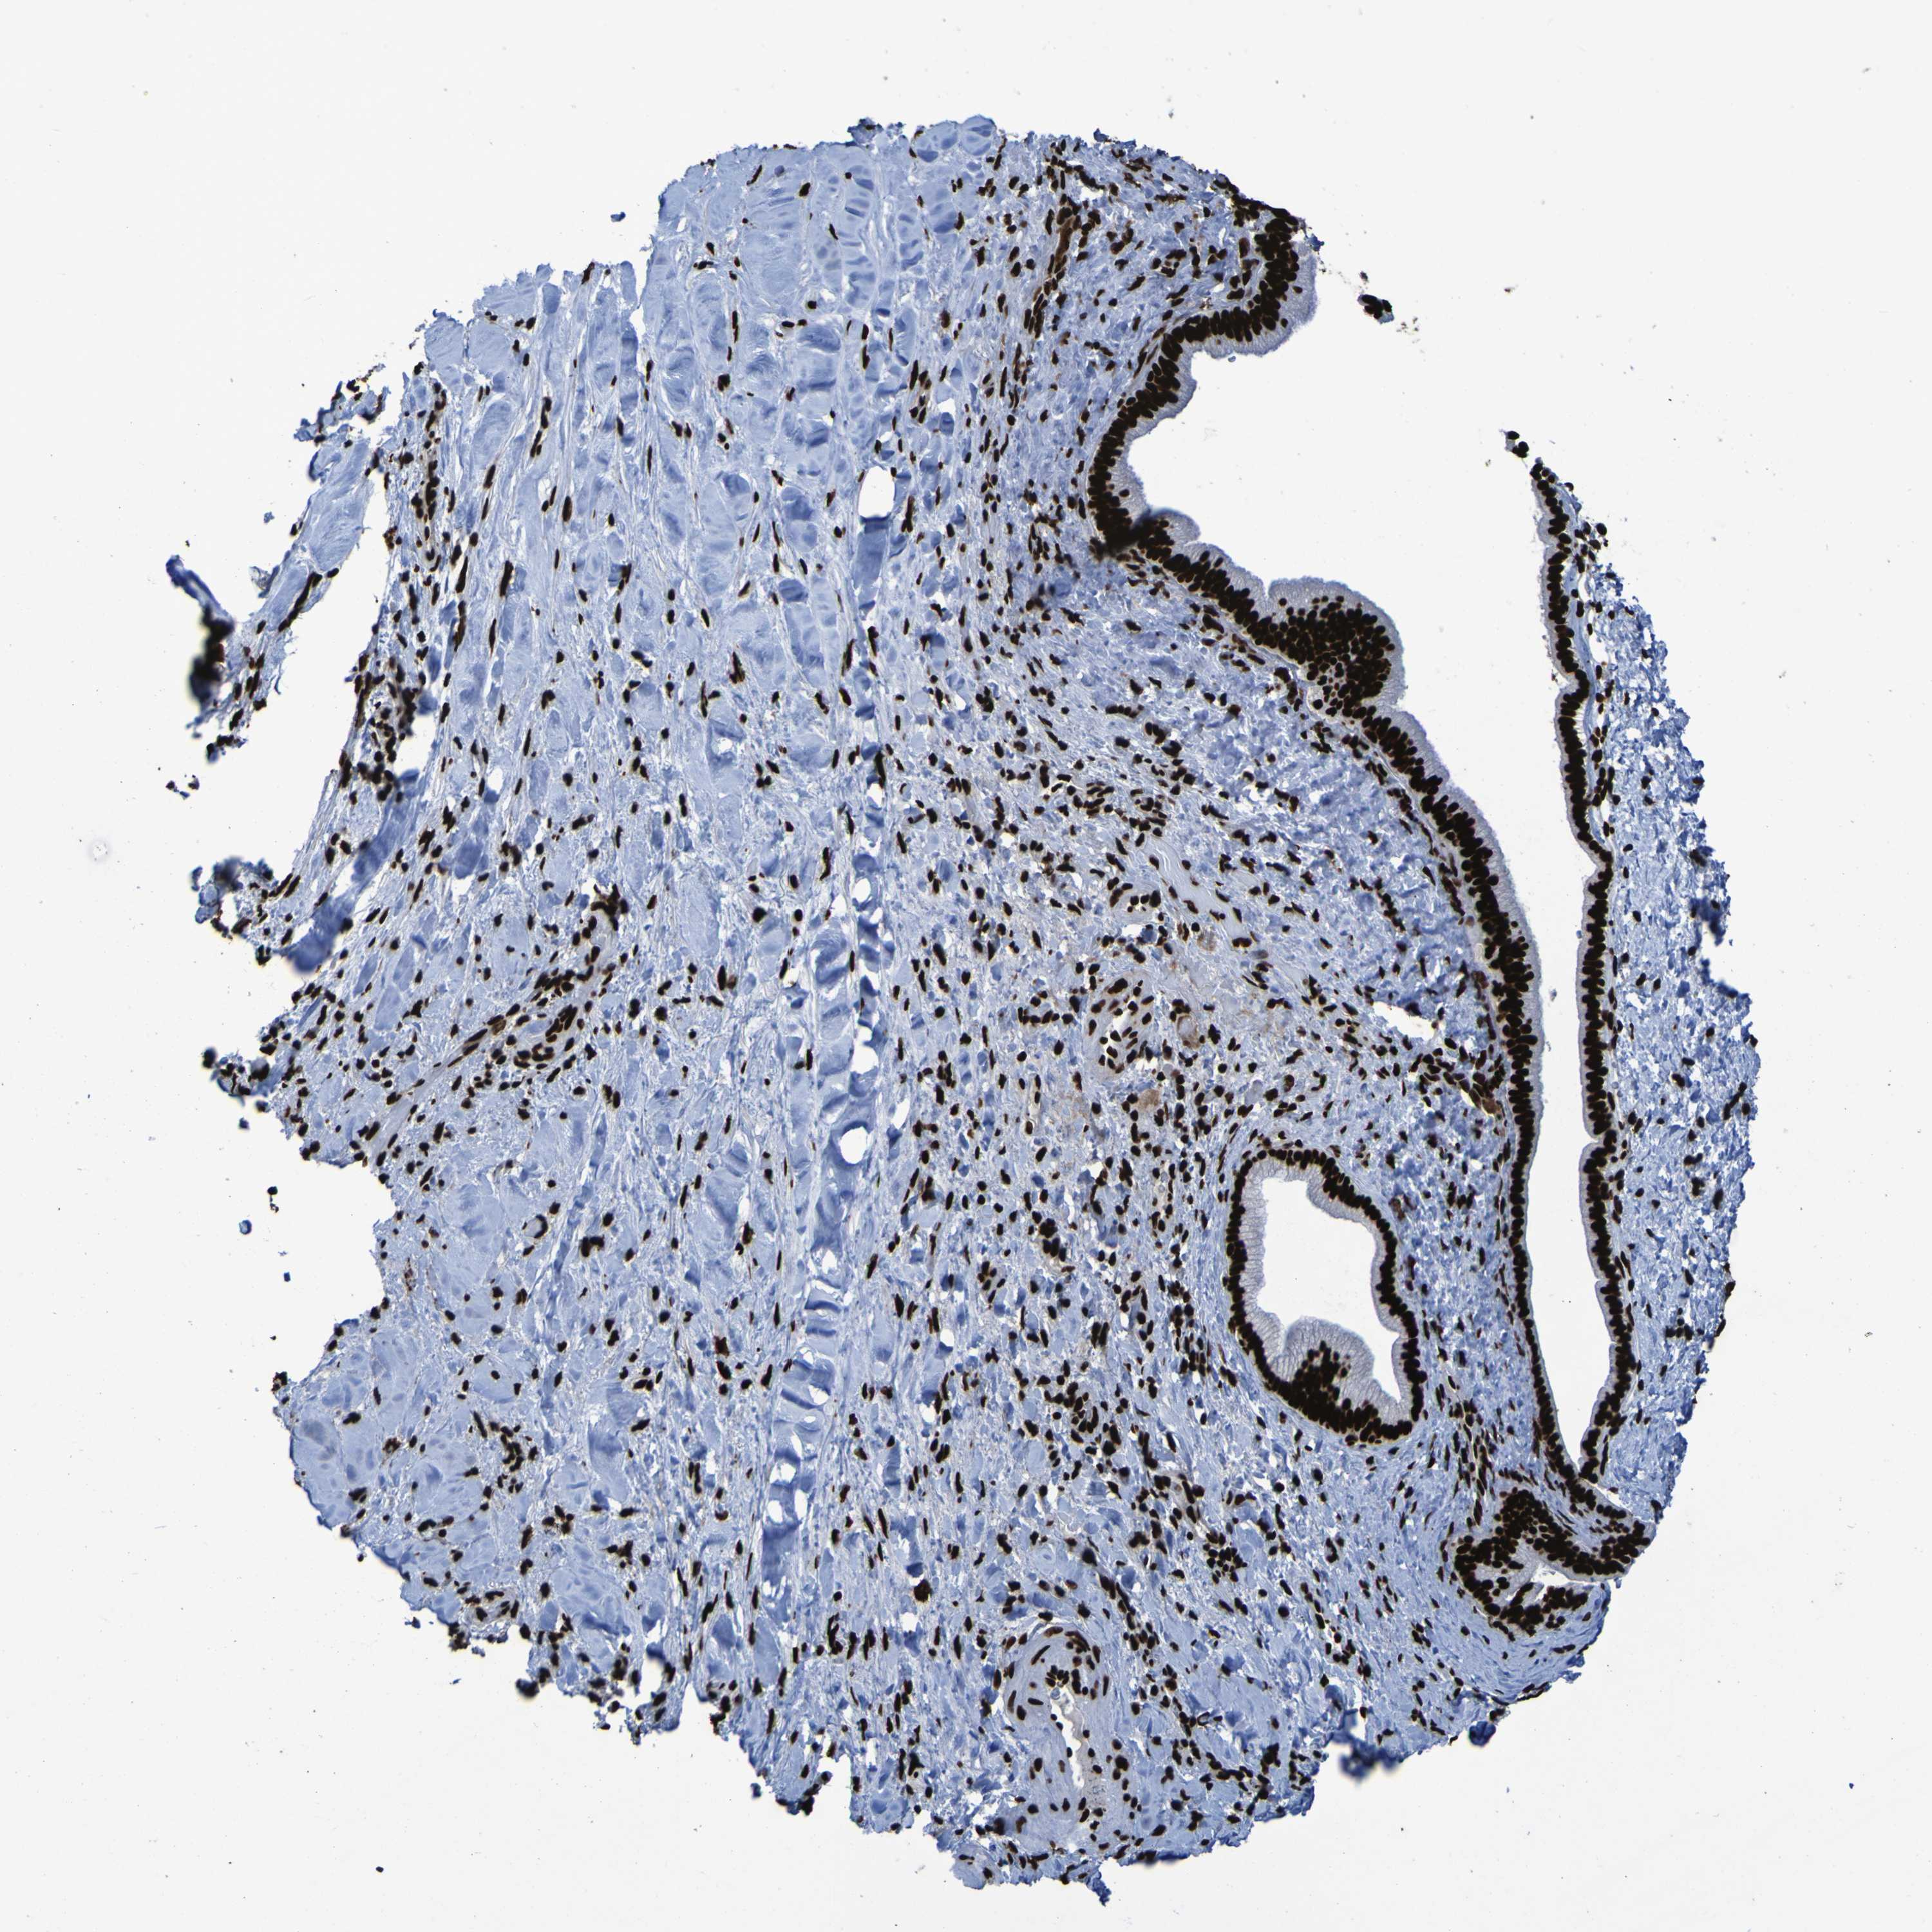

LIVER CANCER - Protein expressioni

A mouse-over function shows sample information and annotation data. Click on an image to view it in a full screen mode. Samples can be filtered based on level of antibody staining by selecting one or several of the following categories: high, medium, low and not detected. The assay and annotation is described here.

Antibody stainingi

Antibody staining in the annotated cell types in the current human tissue is reported as not detected, low, medium, or high, based on conventional immunohistochemistry profiling in selected tissues. This score is based on the combination of the staining intensity and fraction of stained cells.

Each image is clickable and will lead to virtual microscopy that enables deeper exploration of all samples and also displays staining intensity scores, fraction scores and subcellular localization as well as patient and tissue information for each sample.

Antibody HPA011384

Antibody CAB012983

Staining

High

Medium

Low

Not detected

Intensity

Strong

Moderate

Weak

Negative

Quantity

>75%

75%-25%

<25%

None

Location

Nuclear

Cytoplasmic/membranous

Cytoplasmic/membranous,nuclear

Cholangiocarcinoma

Carcinoma, Hepatocellular, NOS